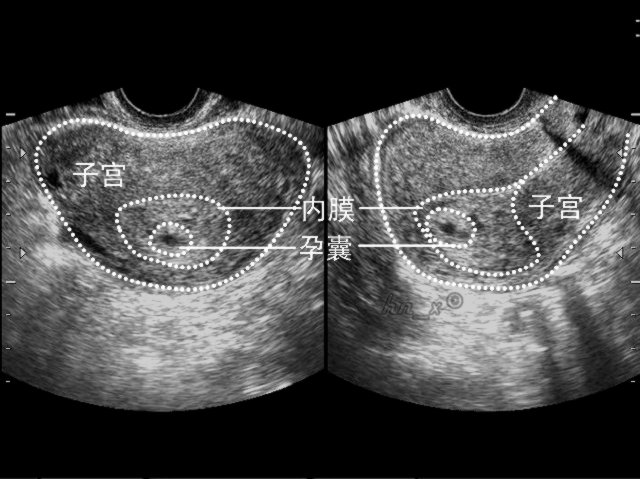

1.孕4-5周:可以看见孕囊,5周左右可以看见原始心管搏动。